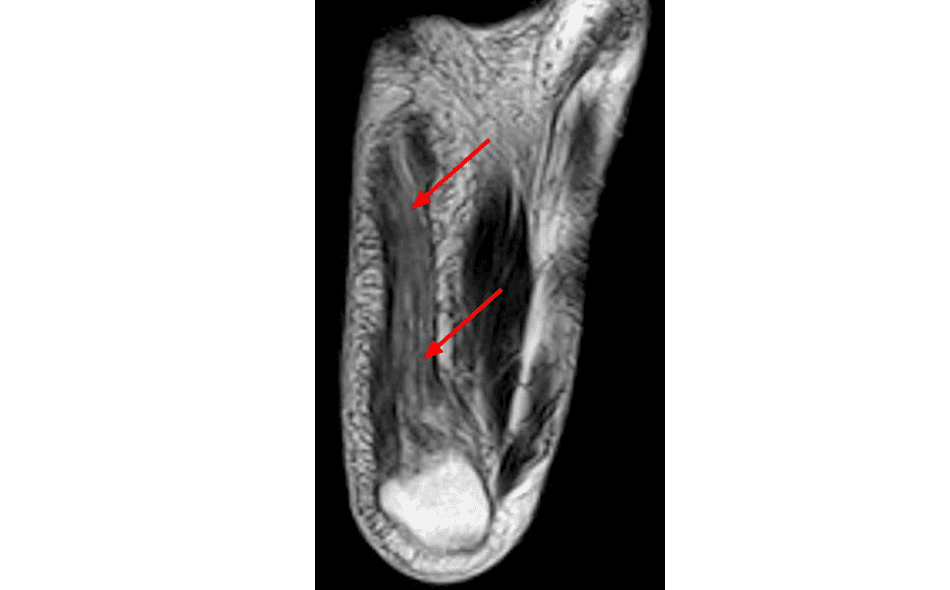

Foot Muscles Mri / foot mri t1 coronal image : The extrinsic muscles are located in the anterior and lateral compartments of the leg.. A magnetic resonance imaging (mri) was performed on a normal subject; Bone contusions, osteonecrosis, marrow oedema syndromes, and stress > fractures) > synovial based disorders ( e.g. In our study, the foot muscles were evaluated differently applying mri and ultrasonography. Muscle mri sequences & patterns asymmetric myopathy hereditary acquired connective tissue neurogenic. | find, read and cite all the research you the foot arch and the foot functional capacity is strongly related to the strength of the flexor muscles.

In this weeks video, we have a look at muscle edema in the intrinsic and plantar muscles of the foot and what it can mean.patreons can access original dicom. Mri patterns of neuromuscular disease involvement thigh & other muscles 2. First of all they act upon the metatarsophalangeal joint of the big toe, leading to the abduction. A magnetic resonance imaging (mri) was performed on a normal subject; Mri and ultrasound have been utilised in the assessment of the plantar intrinsic foot muscles.

This article reviews the use of magnetic resonance imaging (mri) in the evaluation of the foot, including a discussion of bone and cartilage abnormalities The extrinsic muscles are located in the anterior and lateral compartments of the leg. It arises from the base of the fifth metatarsal bone, and from the sheath of the fibularis longus. Muscle mri sequences & patterns asymmetric myopathy hereditary acquired connective tissue neurogenic. In our study, the foot muscles were evaluated differently applying mri and ultrasonography. Mri is particularly useful in visualizing soft tissue lesions that may be compressing a. If you'd like to support us and get something great in return. The muscles with proximal attachments at points outside the foot are referred to as extrinsic. Posted by radiologyer at 8:12 am. Top suggestions for foot muscle anatomy mri. Intrinsic foot muscles differ from extrinsic foot muscles, which have their origins in the leg and the long tendons cross the ankle joint complex 27. Mri also allows to determine the course of the healing process and the success of. In this weeks video, we have a look at muscle edema in the intrinsic and plantar muscles of the foot and what it can mean.patreons can access original dicom.